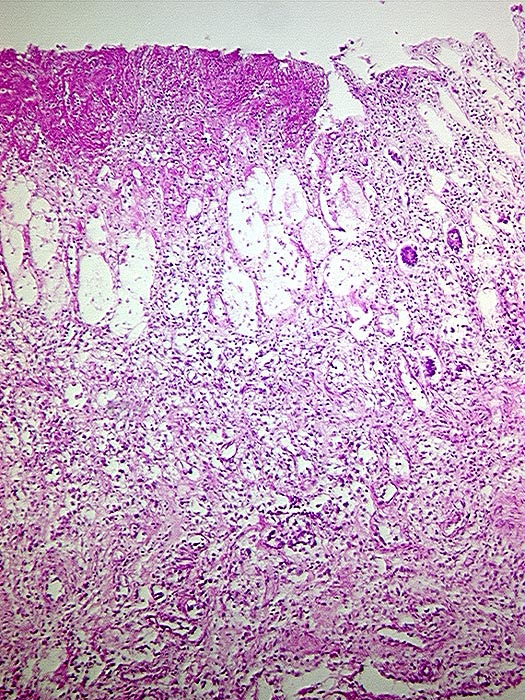

Durch die von den Clostridien ausgeschiedenen Giftstoffe (große clostridiale Zytotoxine: Toxin A und Toxin B) kann eine Diarrhoe mit teilweise sehr schwerem Verlauf entstehen, die lebensbedrohlichen Flüssigkeitsverlust durch (blutige) Durchfälle beinhalten kann. Das Gift des Clostridioides difficile zerstört dabei die Schleimhautschichten und es kommt zu „vulkanartigen“ Fibrinausschwitzungen, die in der Koloskopie als „Katzenköpfe“ beschrieben werden.

Im Ultraschall und in der Computertomographie kann man die langstreckige Darmwandverdickung des Dickdarmes erkennen. Endoskopisch sieht man im Dickdarm grünliche Fibrinbeläge, die teils fleckig, teils flächenhaft zu finden sind.